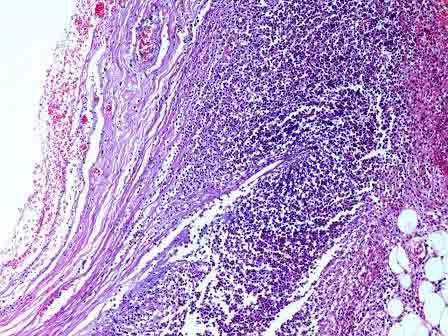

问题 患者男性,42岁,持续性剧烈腹痛3小时伴恶心、呕吐,拟诊“急性阑尾炎”手术。术中见阑尾呈紫黑色,根部破裂。镜检如图,应诊断为 ( )

选项 A.急性蜂窝织性阑尾炎伴穿孔 B.坏疽性阑尾炎伴穿孔 C.慢性阑尾炎伴穿孔 D.阑尾脓肿 E.阑尾腺瘤

答案 B